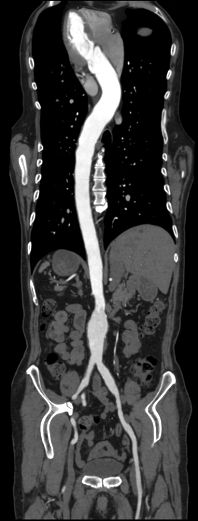

Công nghệ DE tiên tiến: Tích hợp đa dạng kỹ thuật năng lượng kép, hình ảnh rõ nét

Phân tích toàn diện: Cung cấp đồng thời đánh giá định tính và định lượng chuyên sâu.

Giá trị lâm sàng vượt trội: Hỗ trợ nâng cao độ tin cậy trong chẩn đoán và điều trị.

Hình ảnh lâm sàng